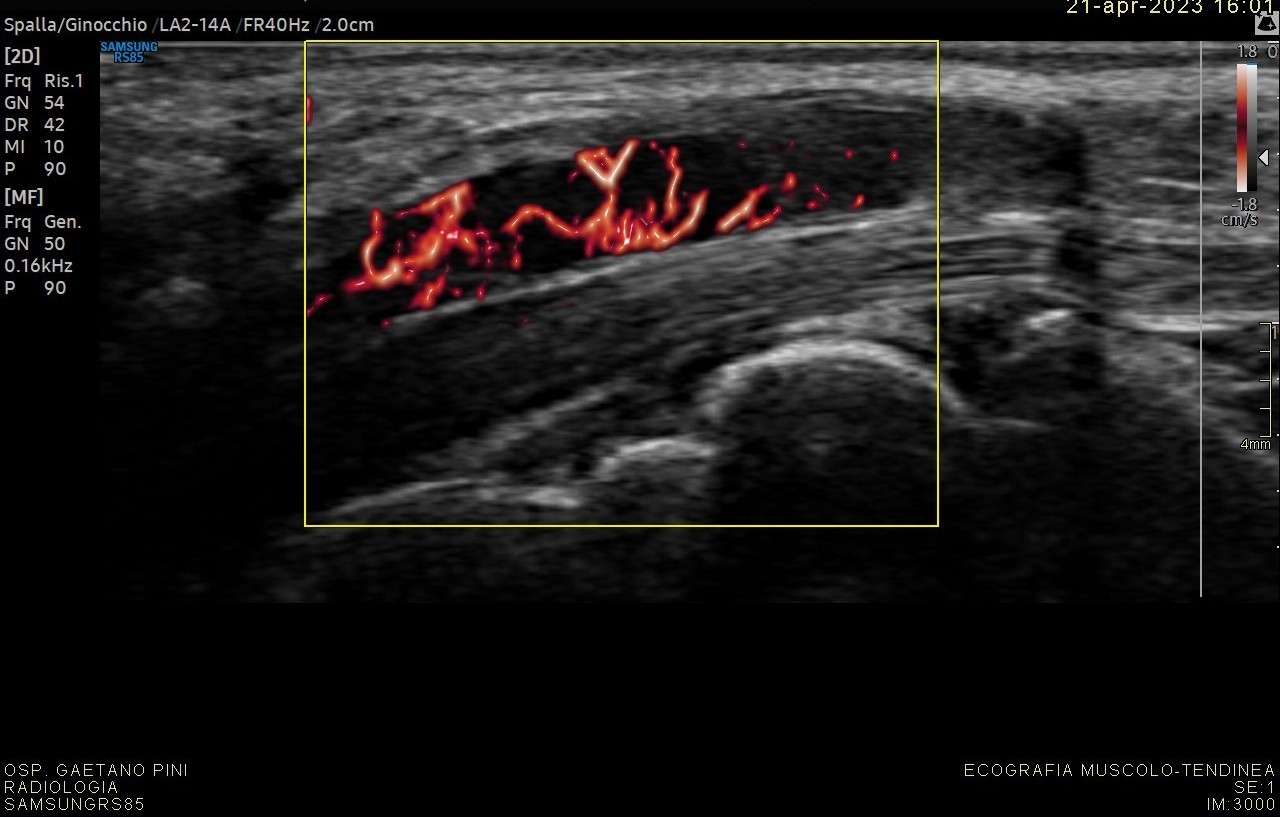

Nuove prospettive di cura per le persone con Parkinson grazie a una ricerca internazionale finanziata dalla Michael J. Fox Foundation for Parkinson’s Research

Il Centro Parkinson e Parkinsonismi dell'ASST G.Pini-CTO di Milano, l’Ospedale Universitario di Würzburg e Newronika SpA ricevono un finanziamento...